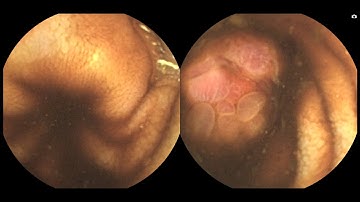

MiroCam MC2000 Double Headed Capsule Endoscopy Ulcer Distal ileum, right side only.